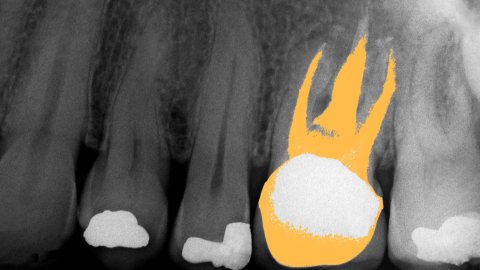

1. When cavities are drilled out, sometimes the fillings don’t stop the decay process. If that goes on long enough, then eventually, the tooth will need to be drilled out/excavated all the way through the root. This removes blood vessels, nerves, and connecting tissue (all of this is known as the pulp). A tooth that has this procedure done to it is effectively dead because the material used in fillings will kill organic cells.

2. The theory is that injecting a tooth with filling made partly of stem cells will stimulate it to heal itself, without the need to resort to those extreme measures.